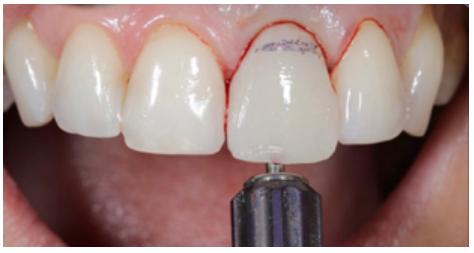

Before starting the provisional screw-retained restoration on the OII, the correct position of the abutment in terms of the provisional prosthesis was verified. The abutment was relined with the provisional through the use of flowable composite (Figures 8 and 9).

Preparation of the emergence profile

To perform the emergence profile (EP), the ideal position of the gingival margin was determined, which had to coincide with the position of the cervical line (amelocemental junction) of the ULCI (Figures 10-13B).